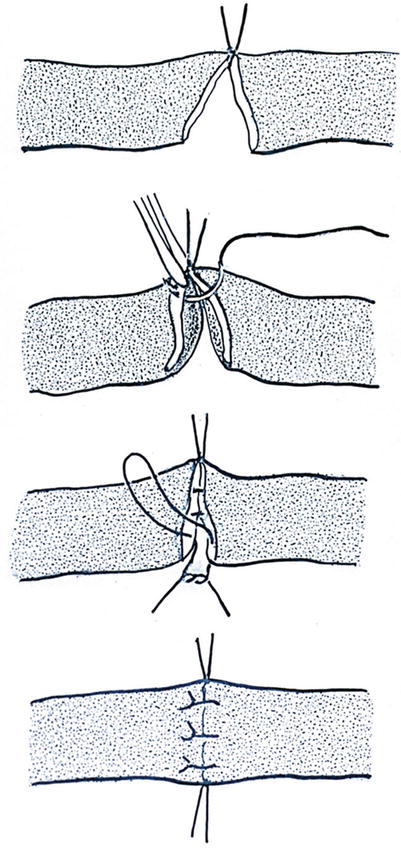

The so-called tension-free anastomosing technique minimizes the forces applied to the vessel wall in oblique direction. It starts with a corner suture opposite to the surgeon. The back wall then is just lifted as far as the needle needs space to fix the back wall on both sides with single stitches leaving the knot on the outer surface. By that way the vessel remains in place without being turned around. Suturing of the back wall is completed with the second corner stitch in front of the surgeon. The front wall is thereafter easily completed by single stitches (Figs. 2.3, 2.4, 2.5, and 2.6) (Baumeister et al. 1981a, b, c).

Fig. 2.3

Scheme of the “tension-free anastomosing technique,” avoiding tension also in oblique direction starting with the first corner suture opposite to the surgeon, back wall gently lifted for single sutures, second corner suture and completing the front wall, no turning the vessel (With permission Baumeister et al. 1981 b from Wiley global permission)

Fig. 2.4

First corner suture

Fig. 2.5

Back wall completed as well as the second corner suture

Fig. 2.6

Lymphatic vessel suture completed